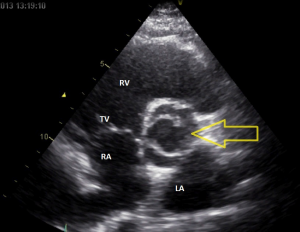

Video 2: echocardiografie korte as opname aortaklep (PSAX), zie ook figuur 3

Op de korte as opname ziet u dat de aortaklep wel degelijk uit twee klepblaadjes bestaat. Het stilstaand plaatje tijdens systole doet denken aan een vissenbek. Er moet dus sprake zijn van een bicuspide aortaklep

Figuur 3: Een stilstaand plaatje van video 2